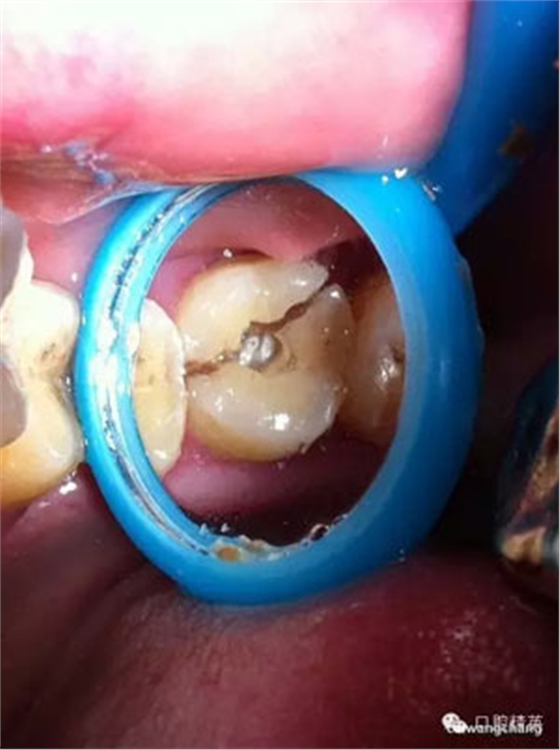

上圖可見該患者的牙斜向裂開,同時沒有做完善的根管治療

先給與根管充填(前提是無根管劈裂),牙膠截斷于根管口

頰部預(yù)備溝槽,準備結(jié)扎絲復(fù)位,現(xiàn)已改為成型夾或血管鉗鉗夾復(fù)位